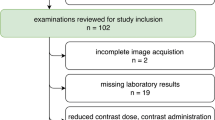

After informed patient consent was waived by the local institutional review board, a structured query to the radiological information system (RIS) was carried out to identify all patients who received ≥ 2 SDCT scans of the abdomen between May 2016 and December 2017. Out of these patients, we identified 79 eligible patients of which 26 underwent biphasic abdominal SDCT thrice and 53 twice. Exclusion criteria were a modified scan protocol in order to reduce contrast media, age ≤ 18 years and renal artery stenosis. The detailed workflow for study inclusion is given in Fig. 1. All patients exhibited a glomerular filtration rate ≥ 30 ml/min. Reasons for examination comprised oncologic staging for melanoma (n = 55), sarcoma (n = 12), lung (n = 8), or GI-tumors (n = 4). Imaging examinations were reviewed for the presence of new ascites or pleural effusion. A significant change in body weight was excluded based on computation of the effective diameter (DE). Anterior-posterior (AP) and lateral (LAT) diameter were determined using an automated script within the Matlab environment (MathWorks) and DE was determined using the formula \( {D}_E=\sqrt{\mathrm{AP}\ x\ \mathrm{LAT}} \) [17].